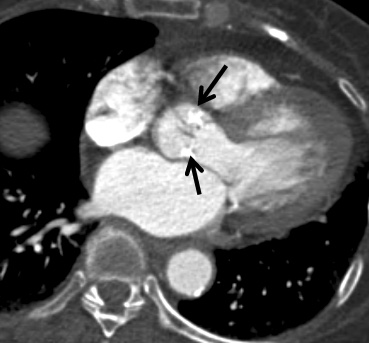

- Fréquente dans la population Agée (dégénéartive vs sur RAA)

- Causée par les calcifications des feuillets

- Pas causé par de simples calcifications annulaires liées à l’âge

- Des calcifications de la valve aortique (60%) de sténose associée

- Dilatation Post-Sténotique de l’Aorte ascendante